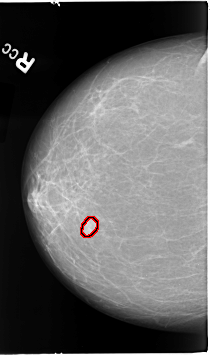

B_3067_1.RIGHT_CC

RIGHT_CC LINES 4608 PIXELS_PER_LINE 2720 BITS_PER_PIXEL 12 RESOLUTION 50 OVERLAY

FILE: B_3067_1.RIGHT_CC.OVERLAY

TOTAL_ABNORMALITIES 1

ABNORMALITY 1

LESION_TYPE MASS SHAPE LOBULATED MARGINS CIRCUMSCRIBED-ILL_DEFINED

ASSESSMENT 4

SUBTLETY 5

PATHOLOGY MALIGNANT

TOTAL_OUTLINES 1